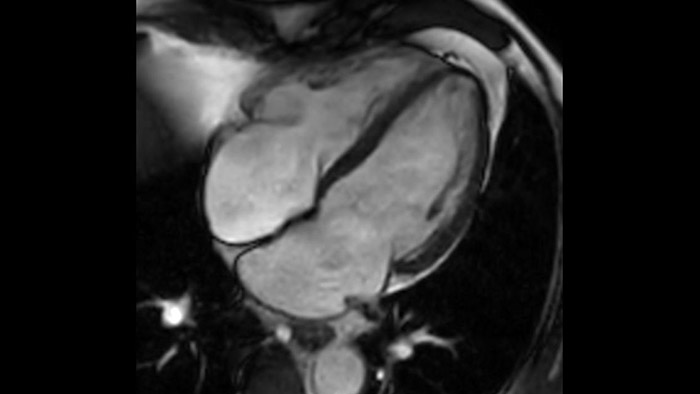

MyoStrain

Transforming the Cardiac Care Continuum

Today's diagnostics often cannot detect heart dysfunction until symptoms occur. MyoStrain utilises segmental strain to measure 48 segments of the heart and provides physicians with a unique diagnostic tool to help identify regional dysfunction before the heart as a whole is affected.